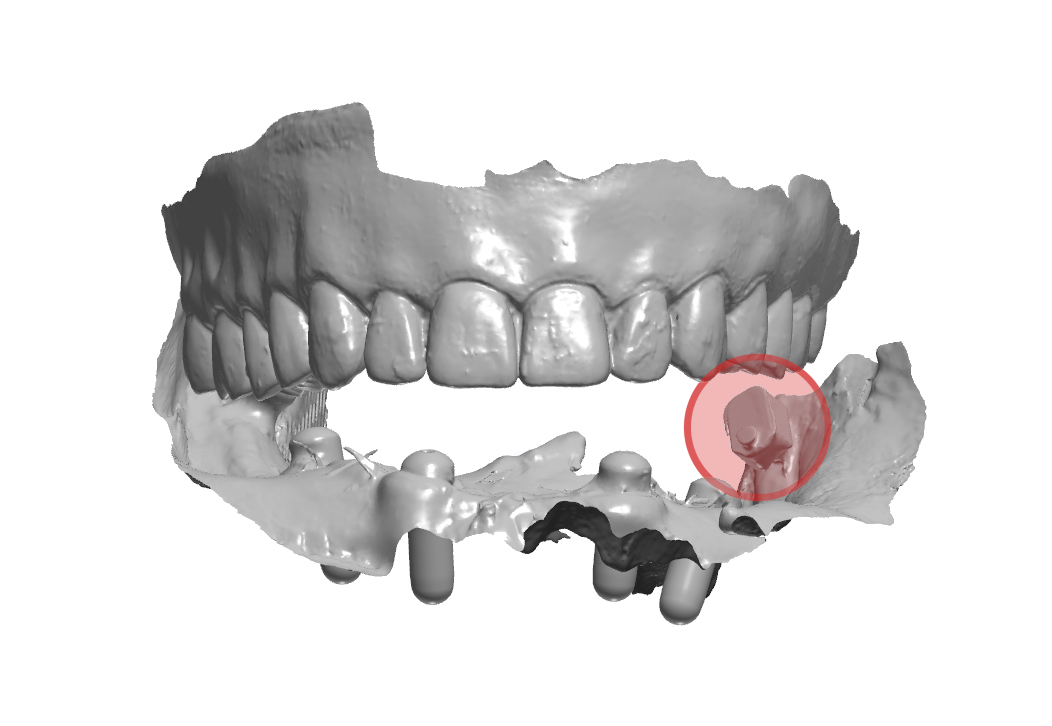

rendering 3D della scansione rilevata in massima intercuspidazione

Fig. 5. (b) rendering 3D della scansione rilevata in massima intercuspidazione, in evidenza lo ScanSke sinistro.

Fig. 8. (a) file .stl della sovrapposizione delle tre scansioni, in evidenza gli ScanSke

Arcate scansionate all’interno dell’articolatore digitale

Fig. 8. (b) Arcate scansionate all’interno dell’articolatore digitale, in evidenza gli ScanSke.